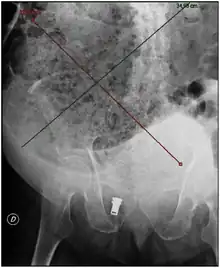

Plain abdominal X-ray showing a large fecal impaction extending from the pelvis upwards to the left subphrenic space and from the left towards the right flank, measuring over 40 cm in length and 33 cm in width. | |